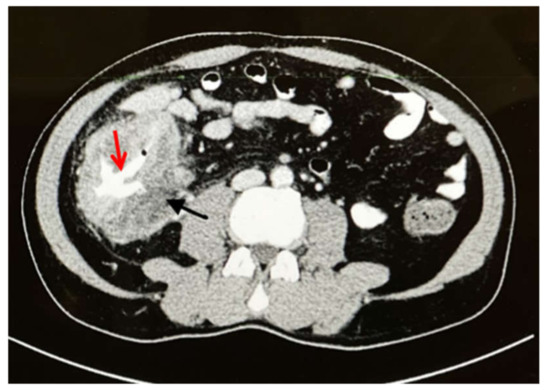

2. Case